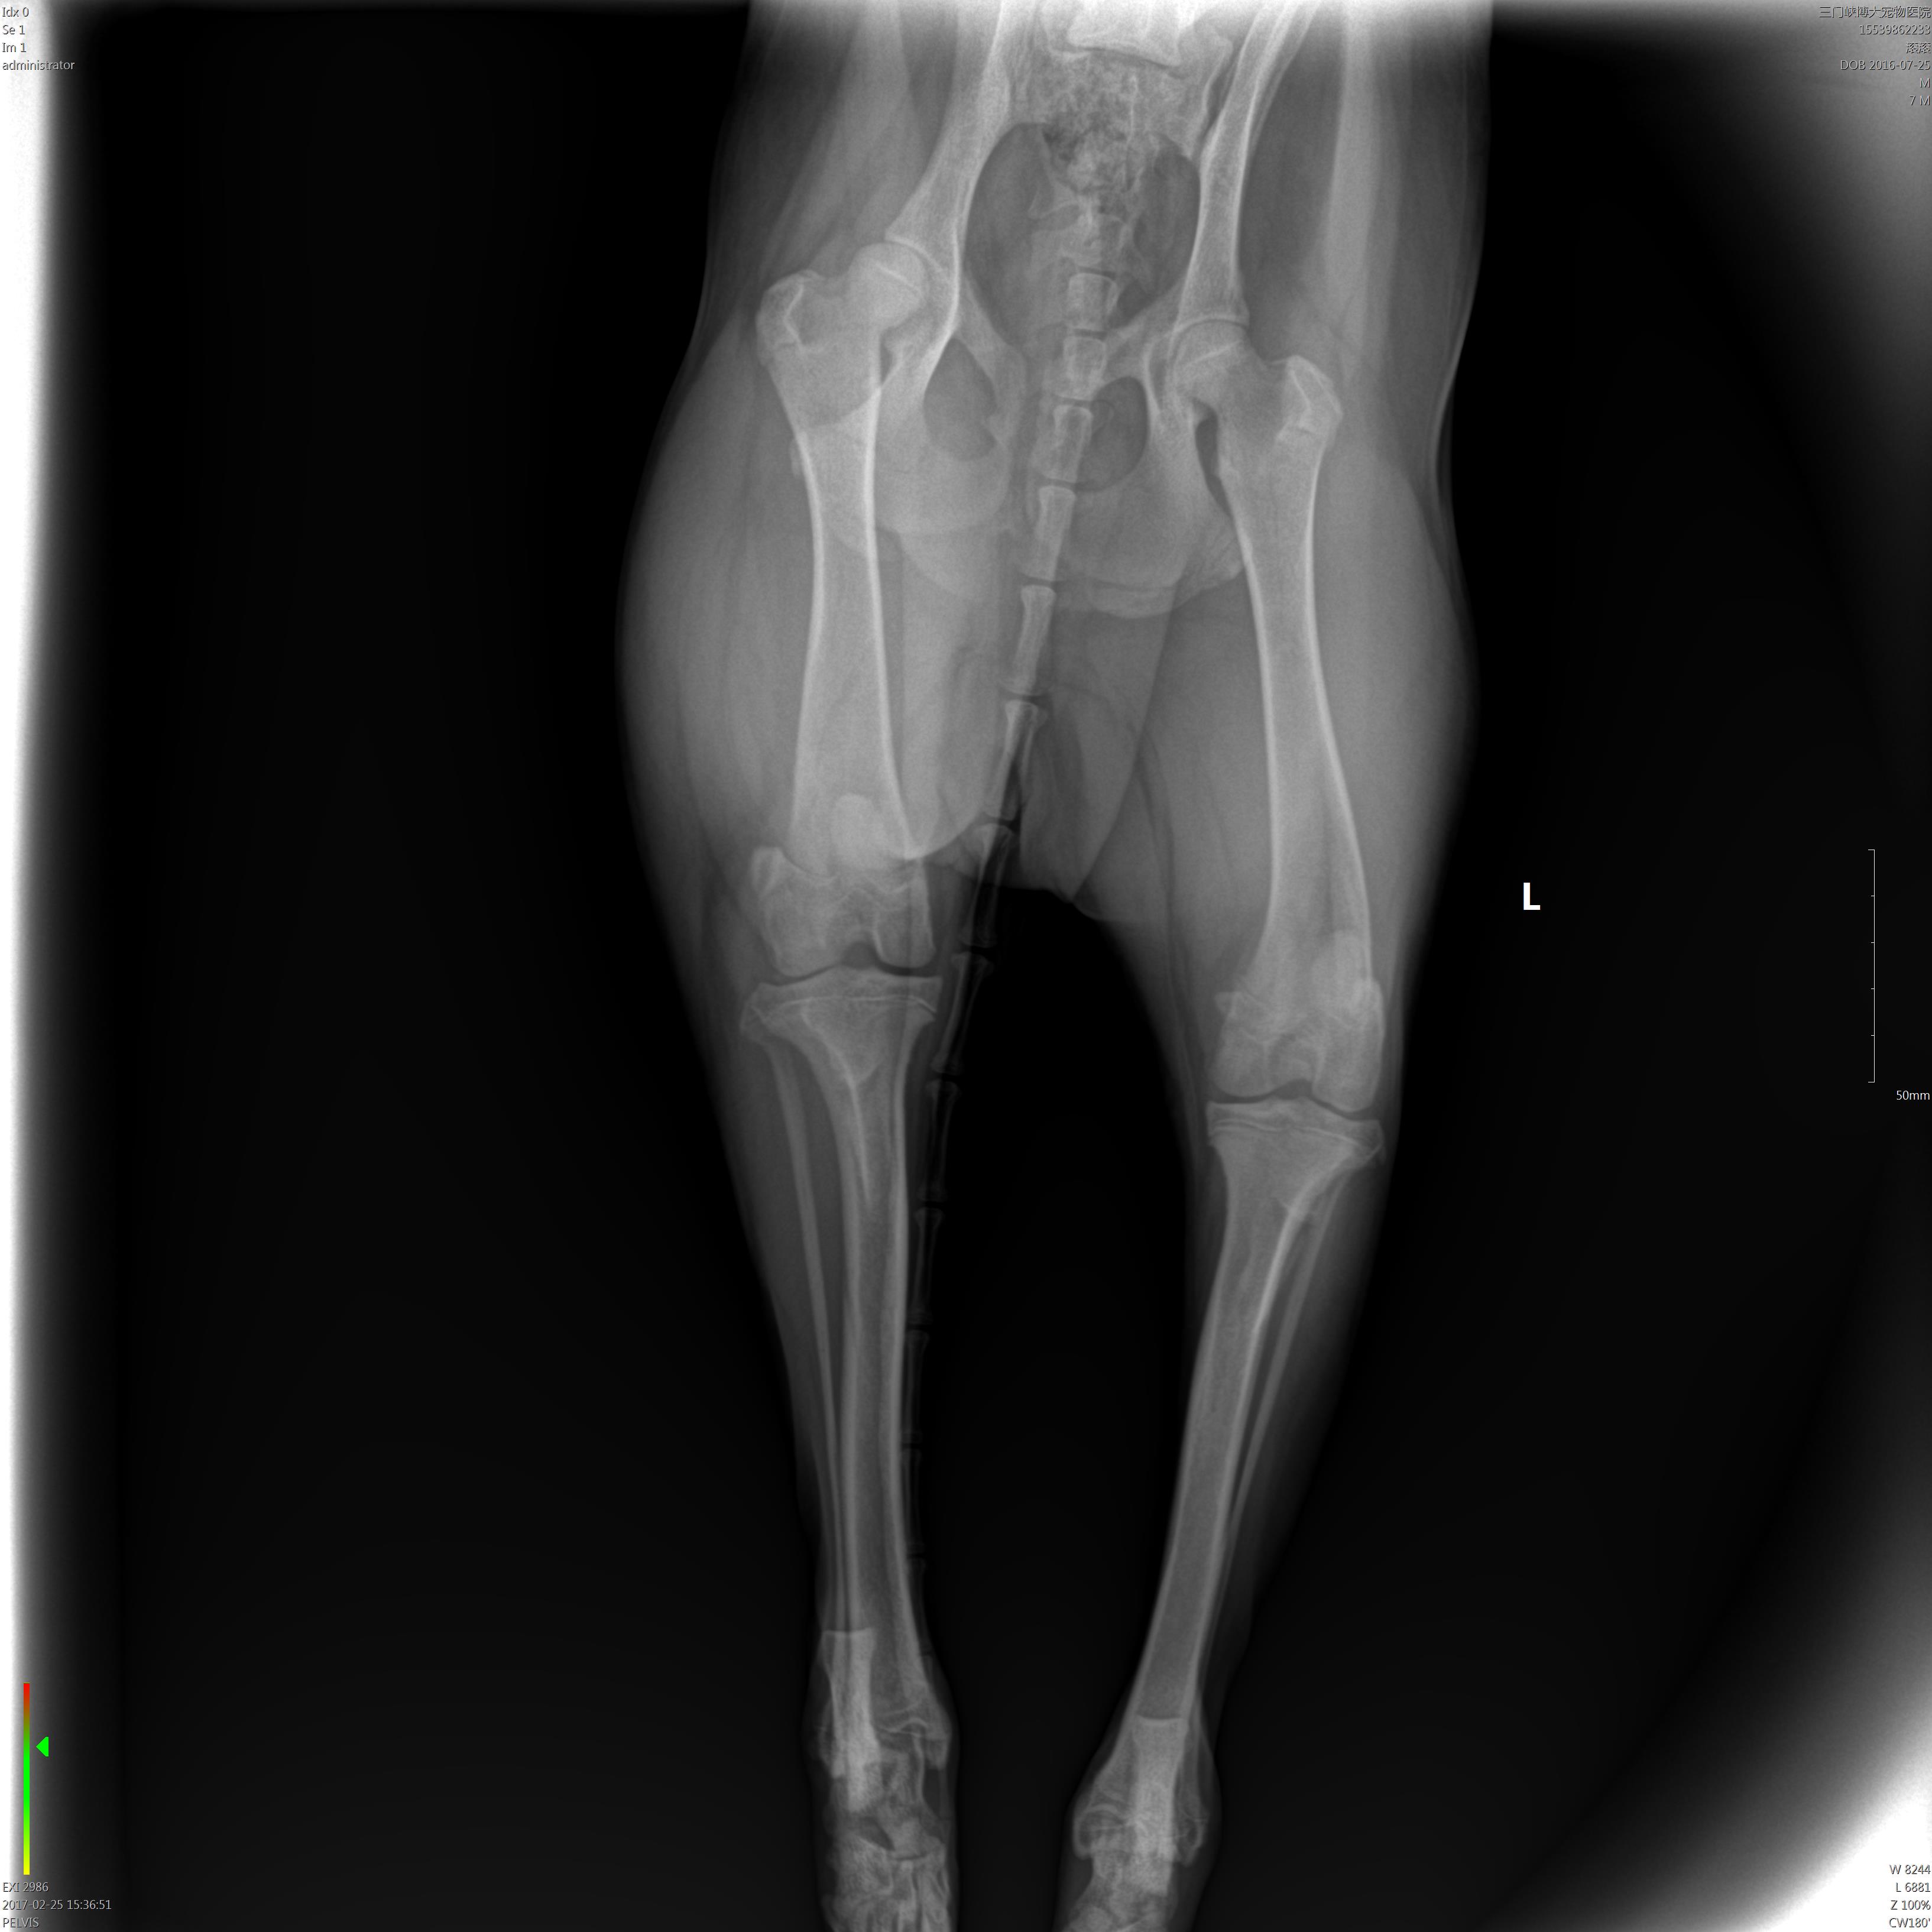

这个片子上骨头是有什么问题么?

是红圈和箭头值得位置的问题么。